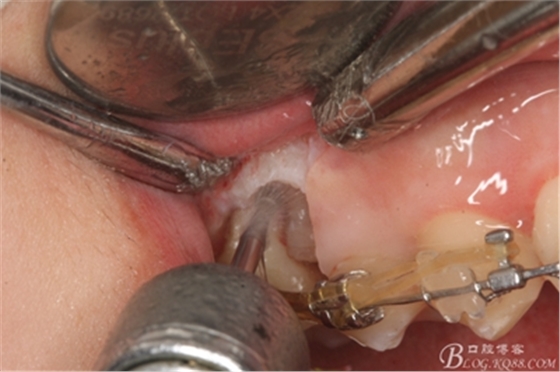

圖11.仔細(xì)考慮之后,在14頰側(cè)做垂直切口,切口長(zhǎng)度僅達(dá)膜齦聯(lián)合處,做小切口。

圖12. 做垂直切口+齦溝內(nèi)切口,形成角形瓣,暴露出15根面。